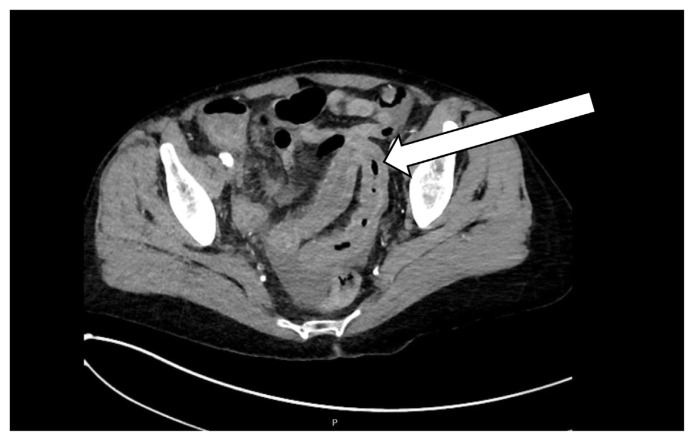

Reactivation of herpes zoster leading to disseminated and visceral organ involvement is an uncommon phenomenon and almost always associated with immunocompromised patients. Visceral herpes zoster is a challenging diagnosis to make as patients typically present with severe abdominal pain which precedes the typical rash of herpes zoster. We describe the case of a 68-year-old female who presented to the emergency department with abdominal pain and was subsequently diagnosed with disseminated herpes zoster and found to have underlying monoclonal gammopathy.